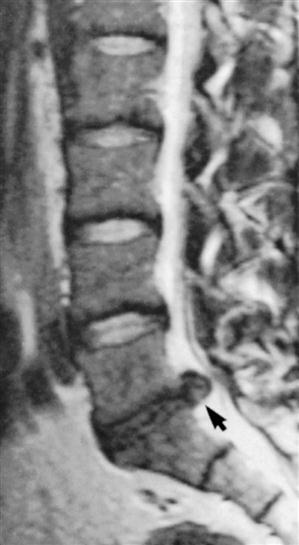

MRI is a noninvasive technique that can be used in several planes (transaxial, coronal, or sagittal) to delineate bony and soft tissues. This technique is commonly used to diagnose tumors, to view the spinal cord within the spinal canal, and to assess for syringomyelia, cord infarction, or traumatic injury.124,268 The delineation of soft tissues is much greater with MRI than with CT.269 For example, with MRI, the nucleus pulposus and the annulus fibrosis are easier to differentiate because of their different water contents, making it the preferred imaging modality for disc disease and radiculopathy (Figures 9-120 through 9-124).23,256,270,271 As with other diagnostic imaging techniques, clinical findings must support what is seen before the structural abnormalities can be considered the source of the problem.255,264,272–274 Up to 30% of asymptomatic patients with no history of low back pain show disc abnormalities.23,275 Things to look for on MRI are disc height, presence or absence of annular tears, degenerative signs, and end plate changes.23